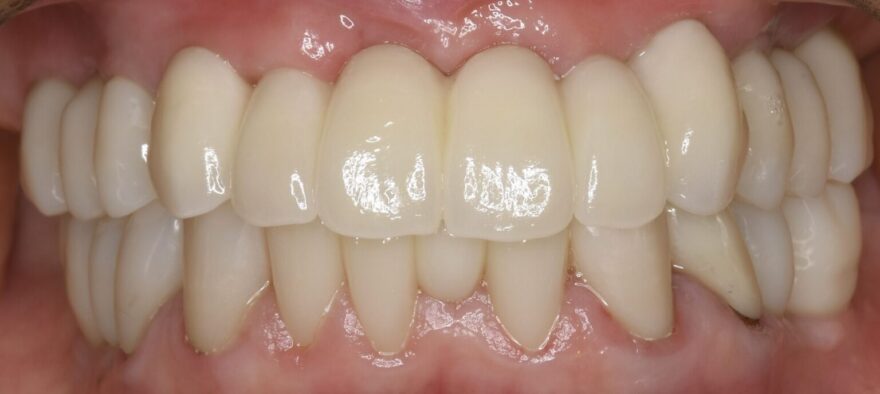

術後の口腔内写真

オールオン4(All-on-4)という、最少4本のインプラントで片顎の全人工歯(10〜12本)を支える固定式インプラント治療のほうが治療自体は早く終了しますが、歯茎が入れ歯のような人工的な見た目になってしまうため、患者様と相談し、より天然歯に近い見た目を作れるボーンアンカードブリッジという方法での治療となりました。

インプラント治療後は、

・口元に自信が持てるようになった

・自然に笑えるようになった

・食事を楽しめるようになった

と、大きな変化を実感されています。

口元の不安が解消されると、表情が明るくなり、印象も大きく変わりました。

不自由なく噛めるようになって食事も楽しくなったとの事で

『こんなに良くなるならもっと早くやればよかったね』とご家族もとても喜んで下さったそうです。